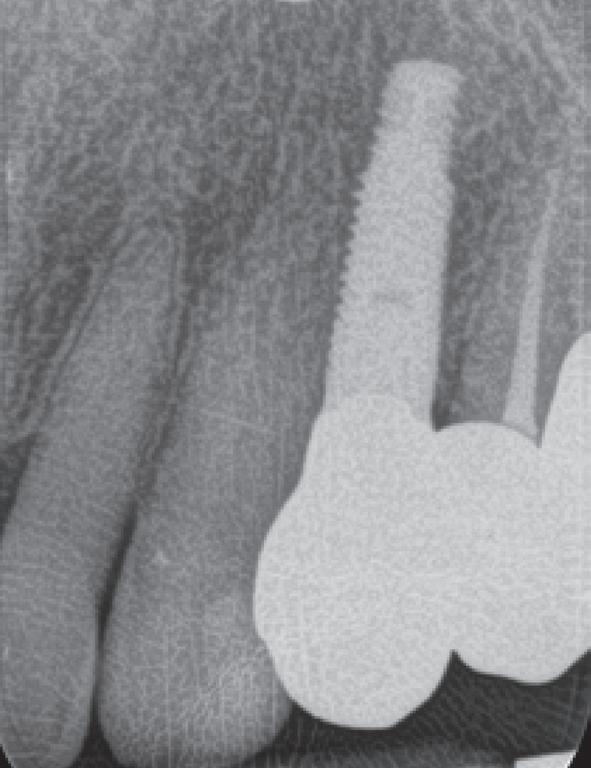

In 1975, one of my patients who was 18 years old became involved in a car accident; he hit the steering wheel with his chin and sustained 2 horizontal fractures in his 31, both quite a way subgingivally. The 41 and 32 were intact. The normal treatment at that time would have required extraction of the 31 and the placement of a partial denture or a bridge to replace the missing tooth.

Knowing that he had nothing to lose, he agreed to let me experiment on him. I extirpated the 31, drilled 10mm past the apex using a sterile Kurer Post spiral drill that matched the diameter of my titanium wire. I sterilised the Titanium using a

Yes, I did stick my neck out, but the result ended being a lot better for the patient than if we had opted for a bridge or a partial denture. The biological cost was negligible and we bought him 30 years of function until a better and more modern treatment became available.

In the current regulatory environment, treatment such as I described is not only illegal and would result in crippling fines being imposed by the TGA, but possibly result in losing one’s right to practice. If I had made a conventional bridge, the teeth either side would have been compromised and possibly lost by now, a partial denture would have caused periodontal problems.